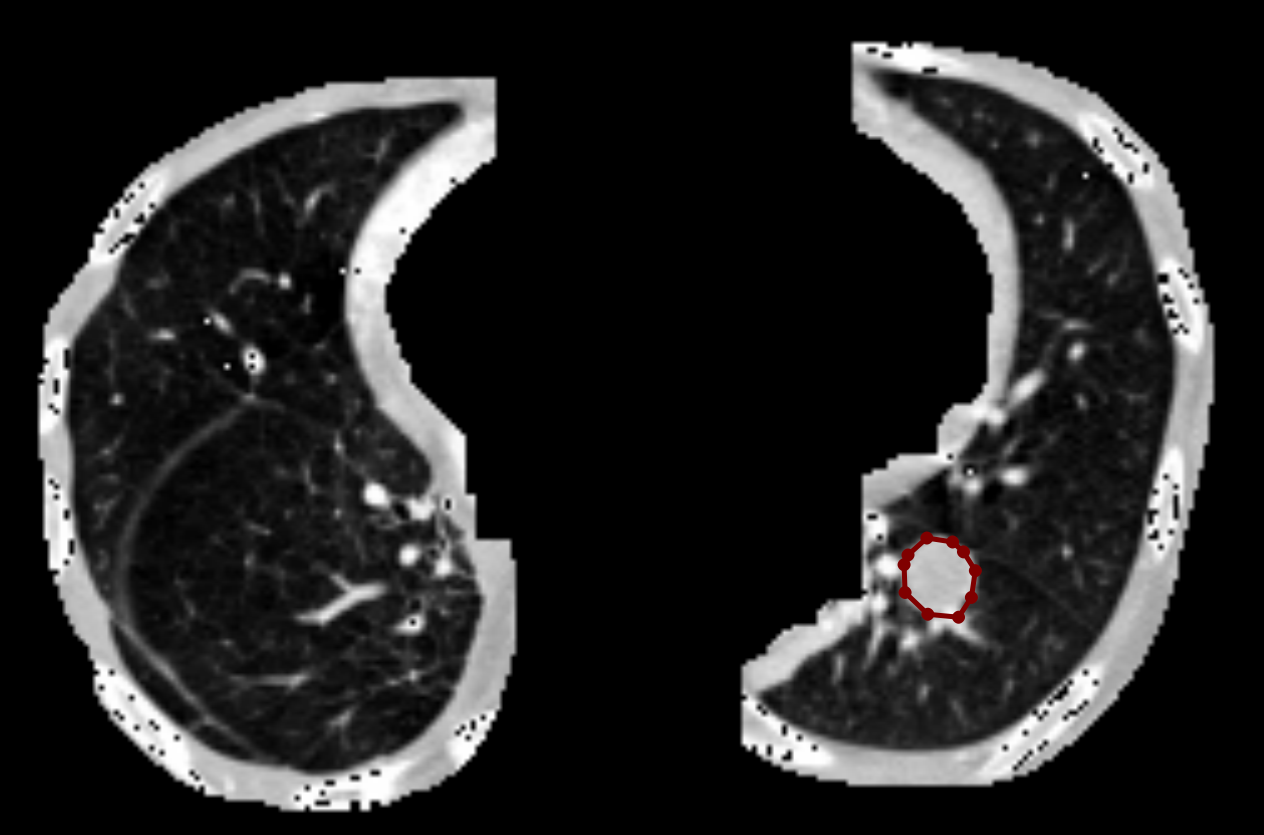

具体而言,本文以目标检测结果中的边界框为参考,结合原始 CT 图像内容,使用 LabelMe 软件对每一个肺结节区域进行逐个手动标注,精确描绘其轮廓,生成对应的 JSON 格式标注文件。每个 JSON 文件中包含了结节边界的多边形坐标信息,可用于自动生成二值掩膜图或直接用于实例分割模型训练。

如下图所示,在每张图像中,我们严格遵循每个结节的实际形态进行轮廓描绘,确保掩膜区域与实际病灶最大程度吻合。这种高质量的人工标注为分割模型提供了可靠的监督信号,有助于提升模型对细小或边缘模糊结节的识别能力。